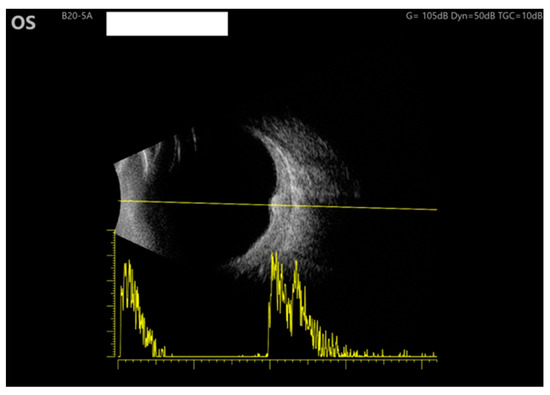

An ultrasound was performed on the left eye, revealing moderate internal reflectivity within the lesion and diffused thickening of the choroid. The B-scan provided detailed imaging, allowing for a thorough evaluation of the area (Figure 3).

Figure 3. Ultrasound of the LE: B scan demonstrates moderate internal reflectivity through the lesion and diffuse choroidal thickening.